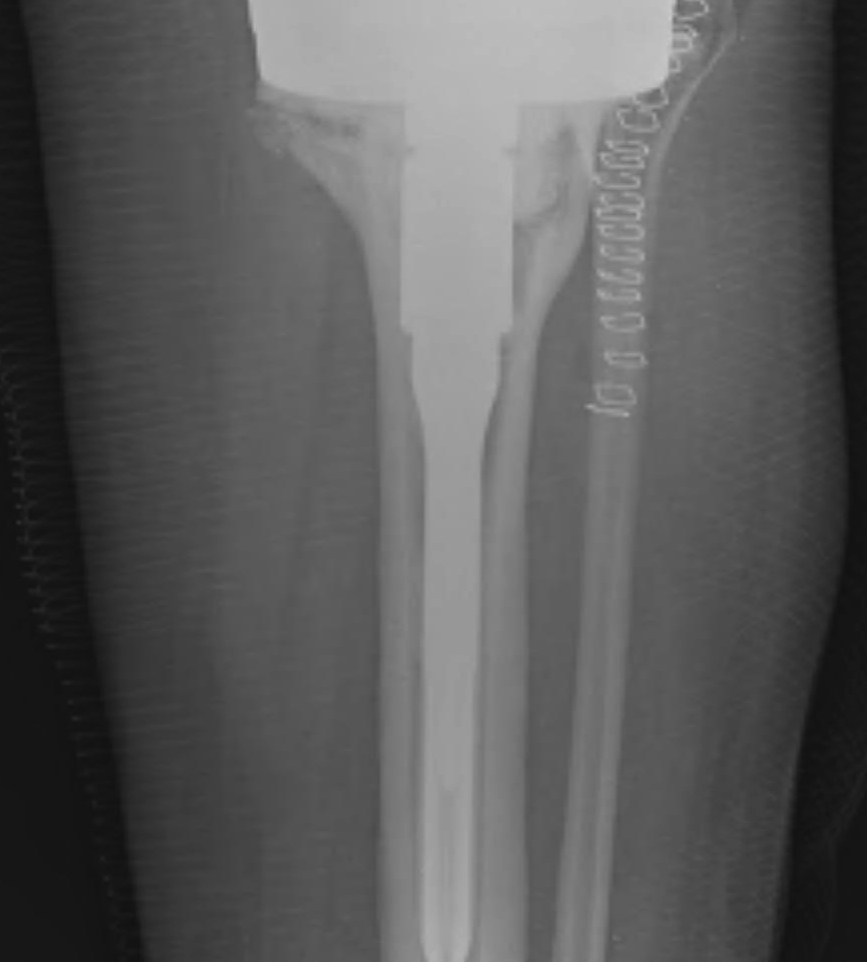

Design

- cemented in metaphysis and condyles

- uncemented in diaphysis

- need to engage diaphysis

- often need offest options from tibial tray

- this is so can implant stem in correct position